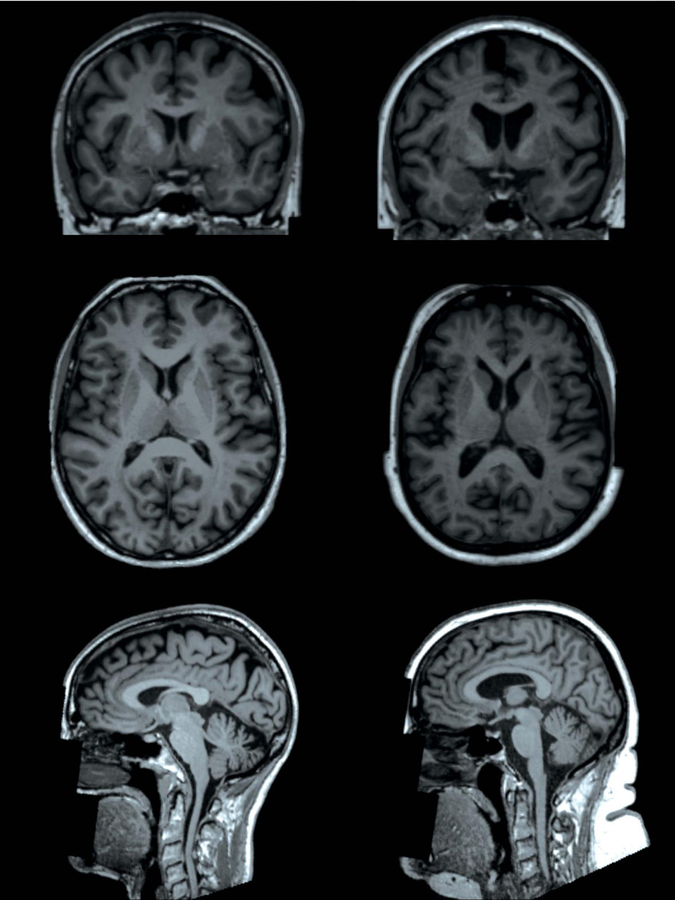

Zum Nachweis zerebraler Adipositas-Effekte nutzten die Wissenschaftler die Daten der UK Biobank Study, einer populationsbasierten britischen Kohorte mit einer halben Million Teilnehmern. Mehr als 12 000 Personen im mittleren Alter von 62 Jahren gingen in die aktuelle Analyse ein. Von diesen waren 18 % adipös und 43 % übergewichtig, schreiben Dr. Ilona A. Dekkers von der Universitätsklinik Leiden und ihre Kollegen. Sie erfassten bei sämtlichen Probanden das Körperfett und untersuchten das Gehirn mittels Magnetresonanztomographie (T1-gewichtet, diffusionsgewichtet).

Die Befunde deuten darauf hin, dass die Adipositas mit einer Abnahme der subkortikalen grauen Substanz einhergeht – allerdings mit Geschlechtsunterschieden. Bei den männlichen Probanden war die gesamte subkortikale graue Masse mit Ausnahme der Amygdala reduziert, bei den weiblichen nur im Globus pallidus. Bei beiden Geschlechtern fanden sich zudem Unterschiede in der Mikrostruktur der weißen Substanz.

Zerebrales MRT von zwei Probandinnen der UK-Biobank-Studie. Eine hat einen Körperfettgehalt von 13 % (links), die andere einen von 49 % (rechts). Bei der adipösen Frau hat die subkortikale graue Substanz ein geringeres Volumen. Zerebrales MRT von zwei Probandinnen der UK-Biobank-Studie. Eine hat einen Körperfettgehalt von 13 % (links), die andere einen von 49 % (rechts). Bei der adipösen Frau hat die subkortikale graue Substanz ein geringeres Volumen. © Radiological Society of North America